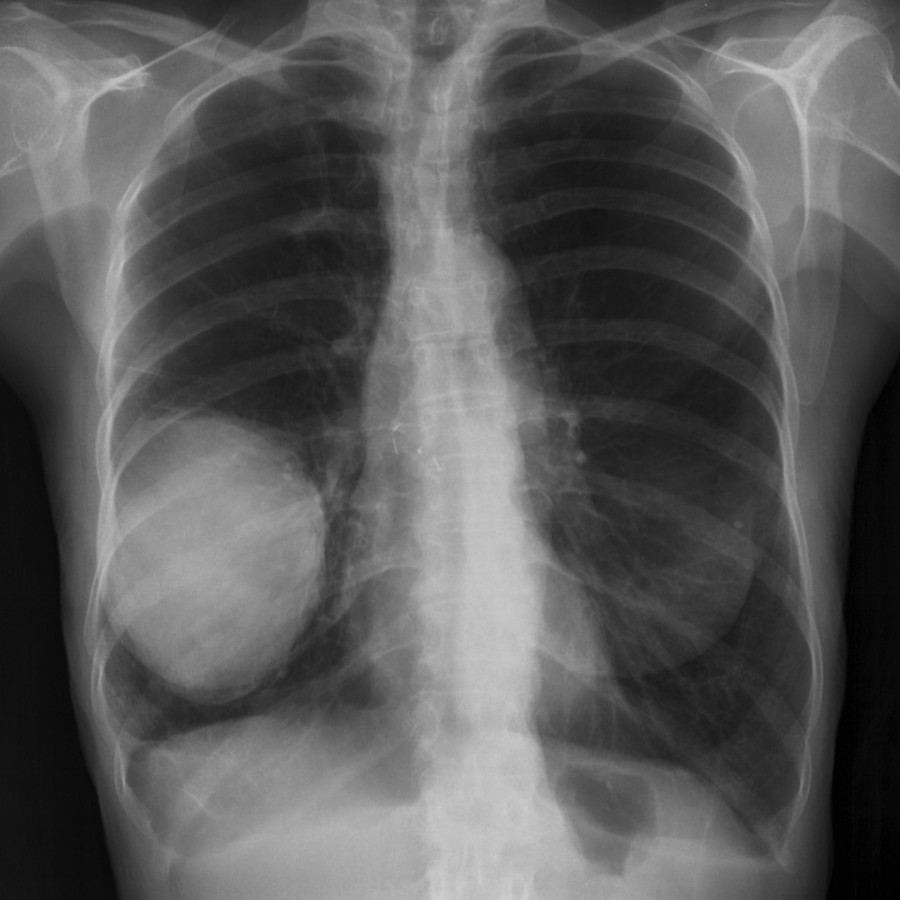

# L'AdenoCa polmonare coinvolge gli Alveoli polmonari. Il conflitto che sta' alla base di questa manifestazione è il conflitto ancestrale di Paura di morire, di non poter più respirare. Condizioni di stress elevato specialmente inFamiglia ed al lavoro, possono precipitare la situazione quando intervenga un episodio scatenante.

In fase attiva si ha proliferazione tissutale in funzione di aumentare la superficie di scambio gassoso. A problema risolto si ha lo smantellamento di questo tessuto ad opera principalmente dei Micobatteri, con la formazione di focolai o caverne tubercolari.